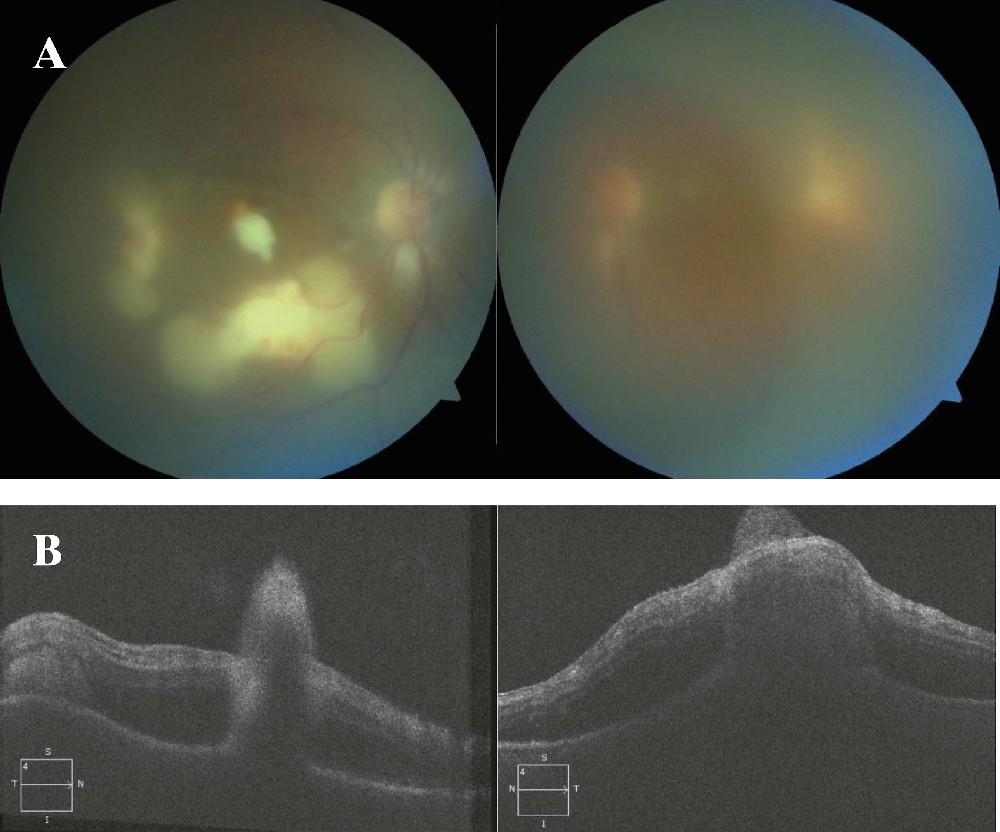

É apresentado o caso de uma paciente do sexo feminino, 77 anos, internada por pielonefrite e tratada com antibóticos de amplo espectro, tendo desenvolvido endoftalmite endógena bilateral presumida por Candida. Foi submetida à vitrectomia via pars plana e injeção intravítrea de anfotericina B, além de voriconazol oral. São abordados, ainda, os aspectos clínicos da endoftalmite endógena por meio de revisão da literatura.